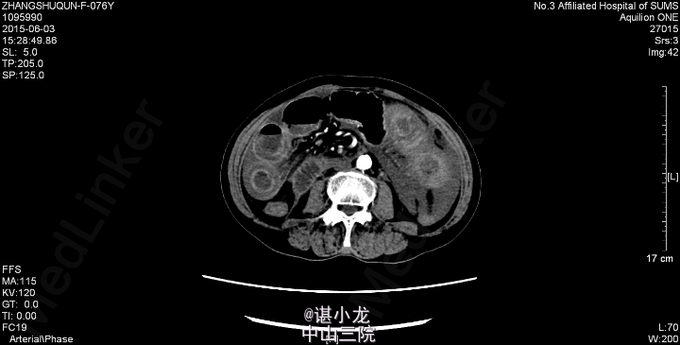

腹平坦,腹部未见曲张静脉、色素沉着,未见手术疤痕,未见胃型、肠型,腹肌软,全腹部压痛、反跳痛,未触及包块,腹部叩诊呈鼓音,肝脾肋下未触及,Murphy(-),肝浊音界叩诊不清,肝区、双肾区无叩痛,腹部移动性浊音(-),肠鸣音3-4次/分。直肠指检未扪及肿物,退指套无血染。 2015-6-3我院急诊腹部CT:空肠扭转,并小肠壁广泛水肿、增厚;腹盆腔中量积液。腹主动脉、双侧髂动脉、双肾动脉、脾动脉硬化。 血常规:白细胞总数16.490x10E9/L,中性粒细胞百分率0.877。凝血四项:凝血酶原时间>200.000sec,活化部分凝血酶时间>180.000sec。大便潜血试验阳性。肝功未见异常,生化示低钠131mmol/L,肌酐260umol/L。